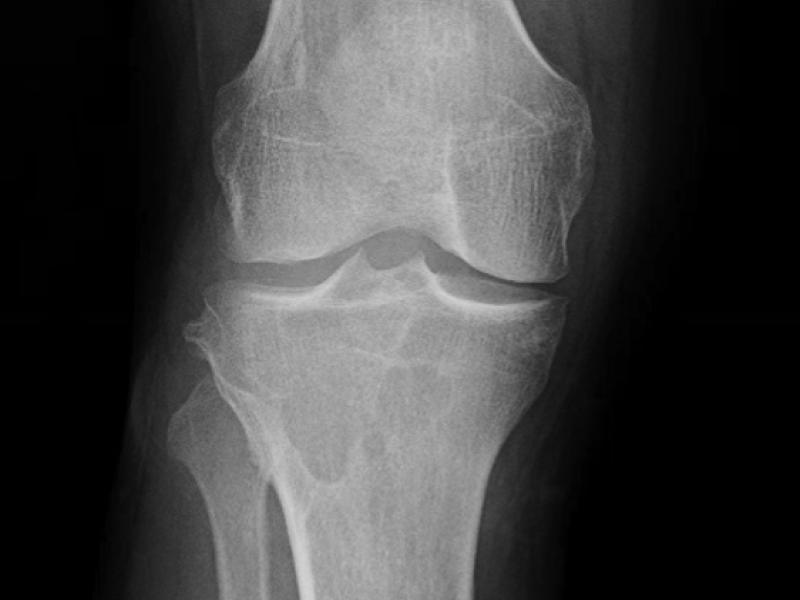

A 44 yo male presents with knee pain for one year. Pain is